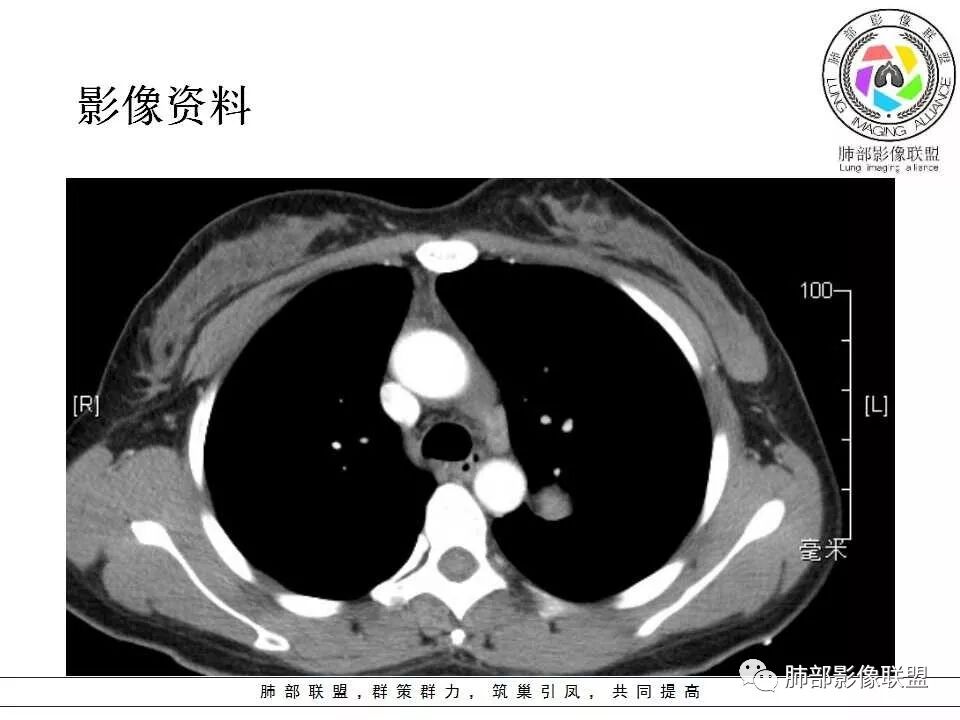

中年女性,发现左肺上叶占位。胸部CT:左肺上叶尖后段孤立卵圆形实性病灶,位于支气管旁,边界清楚,边缘光滑,血管贴边,肺动脉为主征,增强扫描明显均匀强化。考虑:PSP?鉴别CD、类Ca。

青年女性,左肺门占位。定位:跨叶间裂,下叶邻近支气管推压,考虑肺外病变。影像表现:血管贴边,边缘光滑,强化均匀,考虑良性病变,PSP可能大,鉴别CD。

左肺上叶类圆形实性病灶,边缘光滑,可见血管贴边征,病灶与左肺上叶支气管关系密切,左肺动脉相对增粗,增强病灶均匀强化,常规考虑PSP,其次神经内分泌肿瘤不排除。

厚层,只有动脉期。左肺门占位,边界清,动脉期强化比较明显,后段支气管不明确,考虑恶性,类癌可能。psp渐进性强化,动脉期好像没这么明显。

年轻女性,左肺门肿块,边缘光滑,密度较均匀,增强后肿块明显均匀强化,血供丰富,病史提示一年明显增大,也说明富血供,常规考虑PSP,类癌待排。

36岁女性,发现左肺占位1年,时有干咳。CT:左肺门(上叶尖后段?)类圆形结节,边界清,靠前边缘似有GG0,近肺门侧与血管密切接触,似有小凸起,增强见明显均匀强化,似有条片状影往肺门侧血管钻。图片有点少,病灶与支气管的关系看不清(目前的图片与支气管不密切)。随诊结节增大,整体考虑典型类癌可能性大,鉴别硬化性肺细胞瘤。